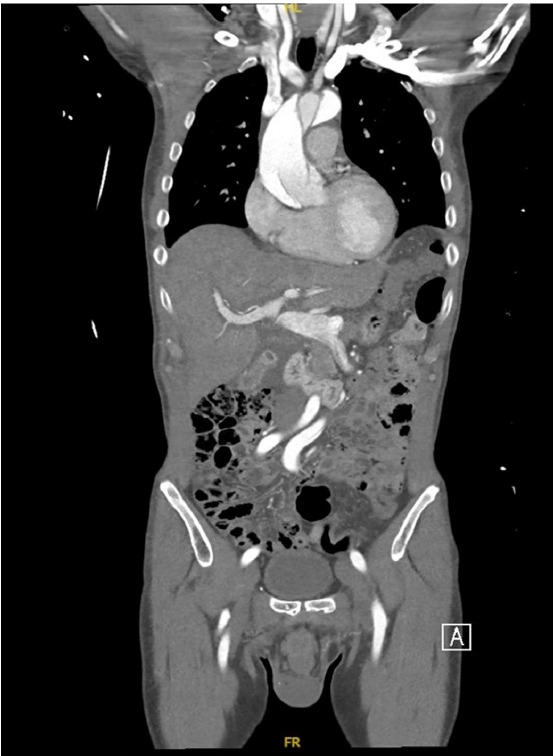

This case concerns a 59-year-old male patient with a medical history of hypertension, chronic renal insufficiency, and autoimmune pancreatitis secondary to immunoglobulin G4 (IgG4)-related disease, who was on chronic steroid treatment. The patient experienced acute onset of lightheadedness, a tingling sensation in both hands, and jaw tightness after masturbating. He was found to have type A aortic dissection. This is the first case of its kind to document an atypical, painless aortic dissection presentation in a patient with IgG4-related disease. This piece explores how the fibroinflammatory sequelae of IgG4-related disease can result in aortic manifestations and discusses the importance of considering a broader differential including aortic syndrome when encountering patients presenting with atypical symptoms.

Abstract Image